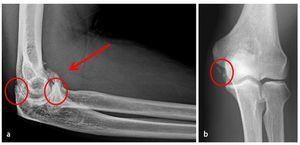

- Diagnóstico radiológico estándar: radiografías del codo en dos planos (fig.3).

Fig. 3 a, b) Vista general sobre el diagnóstico radiológico preoperatorio. En la radiografía estándar de la articulación del codo se observan cambios óseos, incongruencia articular, presencia de osteofitos y cuerpos libres articulares.

Fig. 16 Para la documentación de los resultados de la intervención quirúrgica se realiza un control radiológico en dos planos del codo antes del alta del paciente. a, b) Se pudieron extraer los osteofitos humerales presentes en el preoperatorio (flechas).

- Control radiológico postoperatorio en 2 planos (fig. 16).